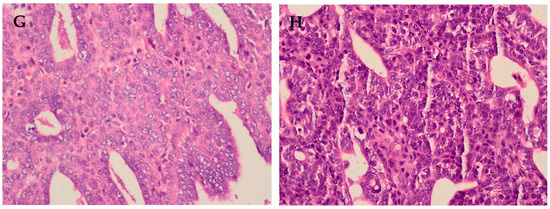

| Tubular differentiation | 2 | 2 | 2 | 1 | 2 | 2 | 2 |

| Nuclear pleomorphism | 3 | 3 | 2 | 3 | 3 | 3 | 2 |

| Number of mitoses | 1 | 1 | 1 | 1 | 1 | 1 | 1 |

| Sum score | 6 | 6 | 5 | 5 | 6 | 6 | 5 |

| Histologic grade | II | II | I | I | II | II | I |